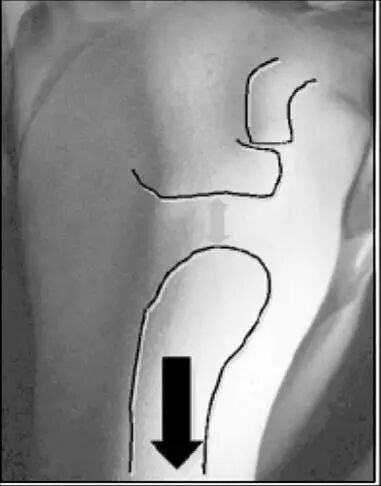

患者坐位,放松肩部肌肉,检查者一手固定肩胛骨,一手在患者肘部施加向下的力,如果肩峰下出现横沟,>2cm者为阳性。阳性结果说明下方不稳,一般均有多向性不稳存在。